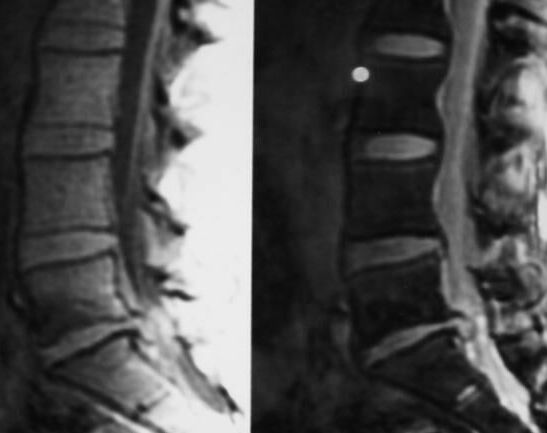

uyuşma, idrar ve gaita retansiyonu ortaya çıkıyor. Spinal MR

incelemesinde L5-S1 diskinin dural keseyi bastıran ileri

protrüzyonu (Şekil) görülerek 60. saatte diskusektomi